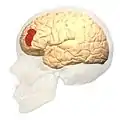

Brodmann area 46, or BA46, is part of the frontal cortex in the human brain. It is between BA10 and BA45.

BA46 is known as middle frontal area 46. In the human brain it occupies approximately the middle third of the middle frontal gyrus and the most rostral portion of the inferior frontal gyrus. Brodmann area 46 roughly corresponds with the dorsolateral prefrontal cortex (DLPFC), although the borders of area 46 are based on cytoarchitecture rather than function. The DLPFC also encompasses part of granular frontal area 9, directly adjacent on the dorsal surface of the cortex.

Lateral view.